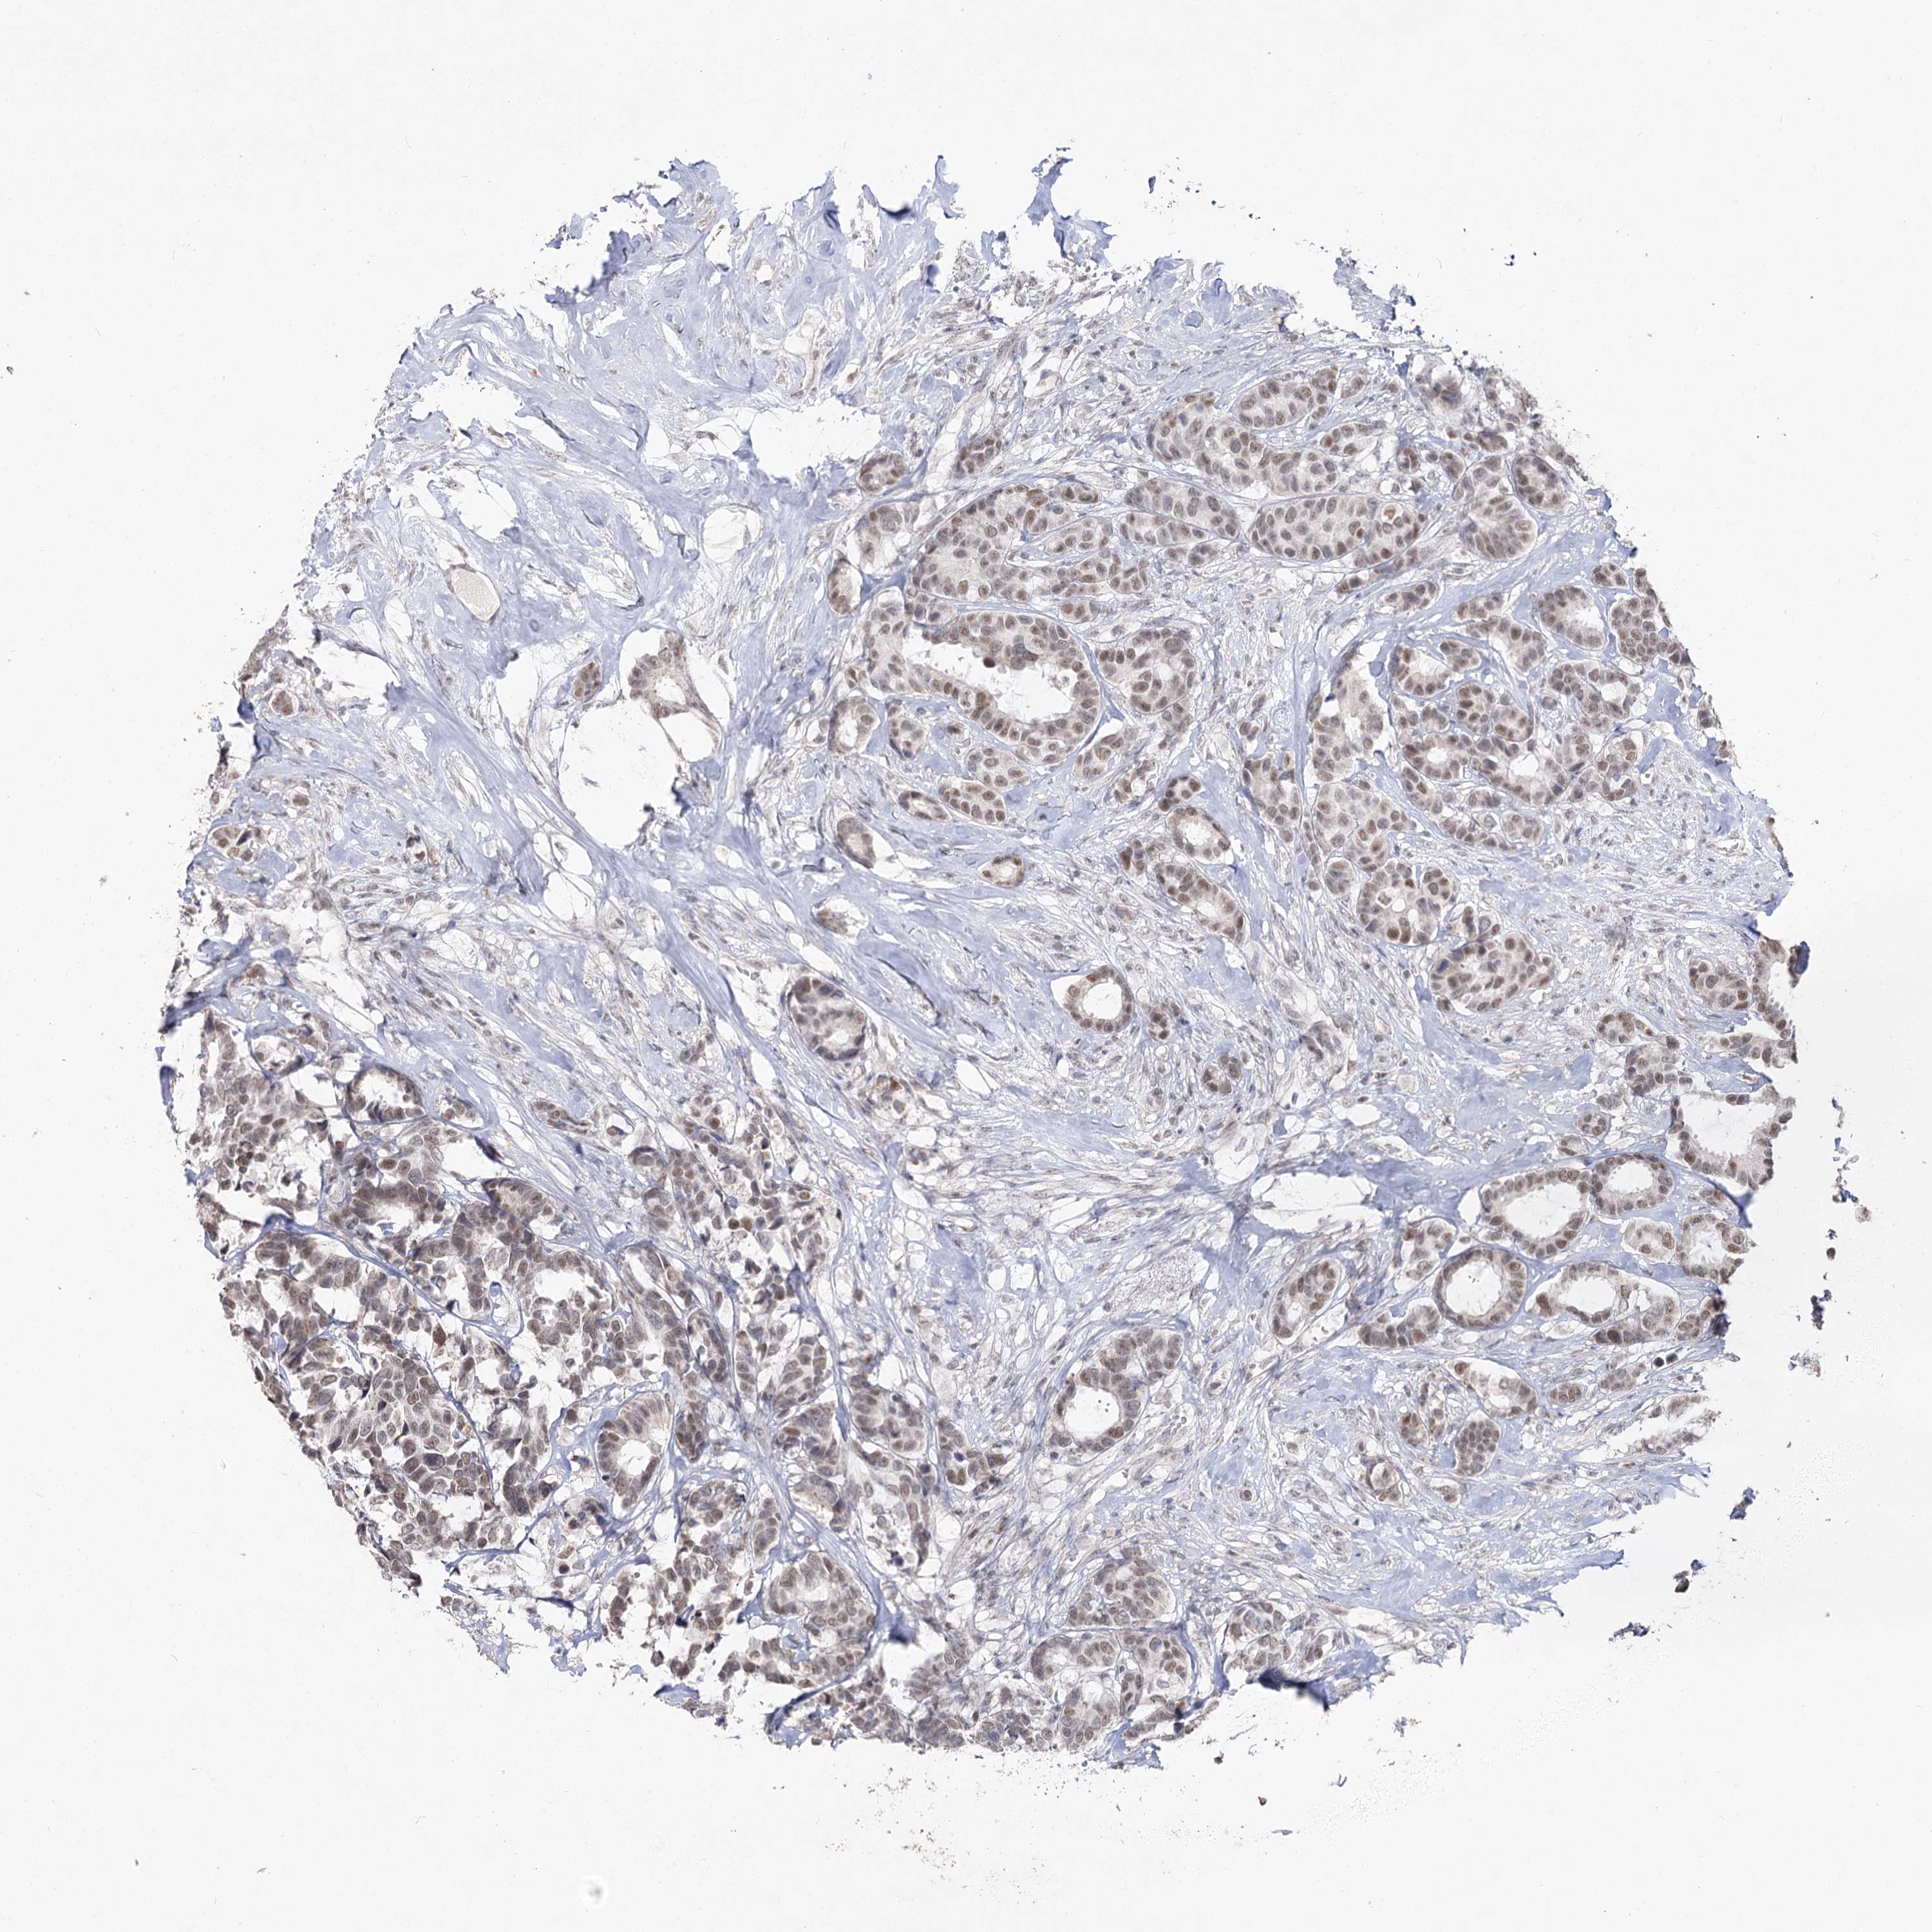

CANCER BREAST CANCER Show tissue menu

BRCA TCGA BRCA VALIDATION PROTEIN EXPRESSION